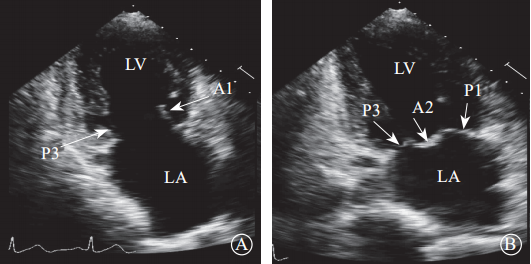

通过采集4个食管中段切面完整显示二尖瓣(图8)。(1)食管中段的四腔心切面,显示A2、A3和P1;(2)食管中段的二尖瓣交界处切面,显示A2、P1和P3;(3)食管中段的二腔心切面,显示A1、A2和P3;(4)食管中段的长轴三腔心切面,显示A2和P2。

图 8 经食管二维超声心动图显示二尖瓣瓣叶各扇叶 A. 食管中段的四腔心切面,显示 A2、A3 和 P1;B. 食管中段的二尖瓣交界处切面,显示 A2、P1和P3;C. 食管中段的二腔心切面,显示 A1、A2 和P3;D. 食管中段的长轴切面,显示 A2 和 P2